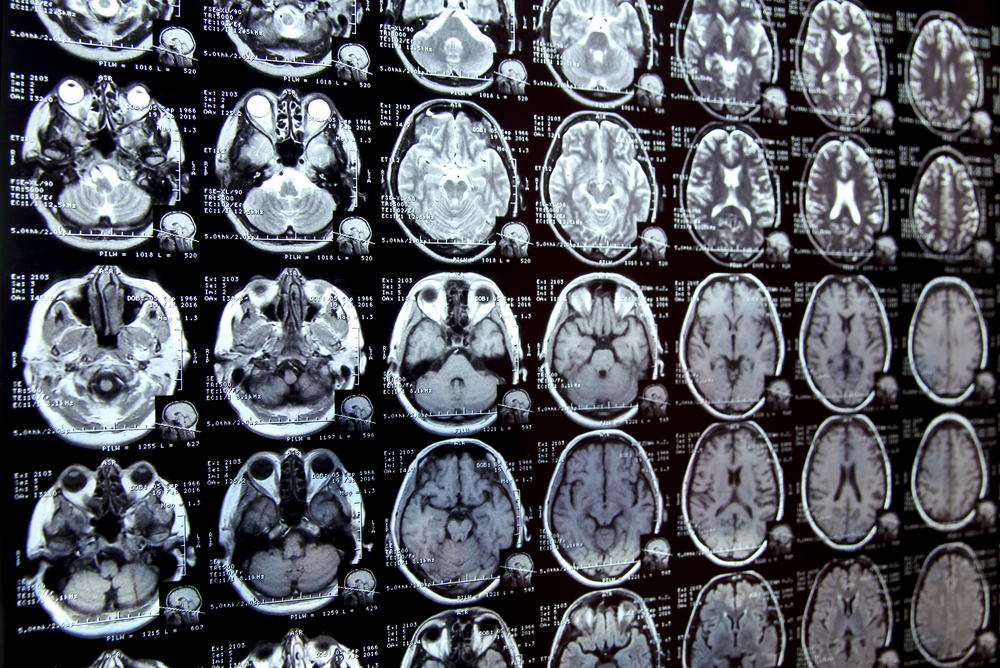

As new owners of the IP rights for a new oncology diagnostic molecular MRI contrast agent, an academic spinoff sought help bringing the device into the clinic. The management team also wanted guidance on determining which companies to approach as future licensees.

A complete review, including a SWOT analysis, was conducted of the MRI contrast imaging market and the opportunity for this new technology.